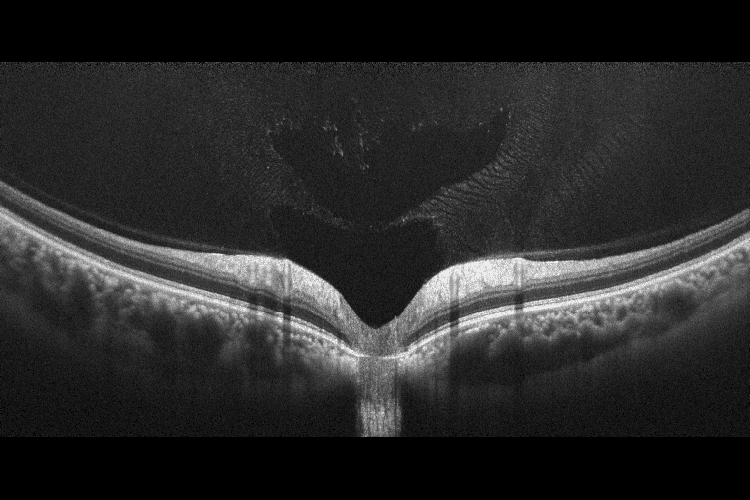

Оптична когерентна томографія (ОКТ) високої роздільної здатності та фотографія сітківки високої чіткості об’єднані в доступному ОКТ-пристрої початкового рівня з невеликою площею та гнучким розташуванням, що пропонує перевагу легкого розміщення в будь-якій кімнаті та навіть розміщення в кут, що дозволяє оптимально використовувати доступний простір за допомогою сенсорного екрану.

Сканування з високою роздільною здатністю

Поєднання ОКТ і ретинальної камери високої чіткості в OCT-R1 робить його ідеальним рішенням для скринінгу та практик із високою пропускною здатністю пацієнтів. Він пропонує широкий спектр високоякісних зображень сканування розміром до 14,7 x 13,4 мм з роздільною здатністю 32,5 МП і спеціальними алгоритмами, які створюють зображення високої чіткості та неперевершеного кольору.

Xephilio OCT-R1 включає функцію усереднення, яка дозволяє комбінувати до 50 множинних сканувань для усунення будь-якого оптичного шуму за допомогою автоматичної сегментації з підтримкою ШІ. Він здатний робити дуже великі ділянки сканування 14,7 мм × 13,4 мм із дуже високою роздільною здатністю 1536 A-сканів у ширину.